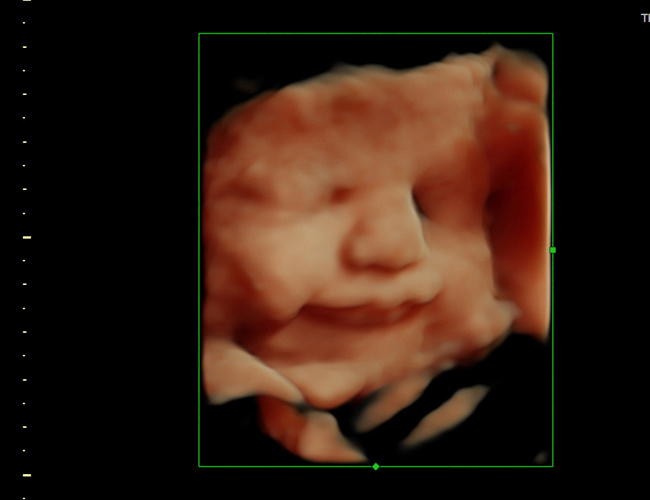

4D Fetal Imaging

HD, 4D and 3D ultrasound in Loving Arms Birth and Wellness Center in Ocala Florida.